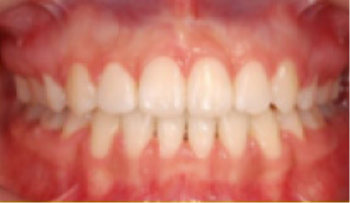

교정치료 Before&After

• 상악 전돌(돌출) 위턱이 앞으로 나옴.

Before

After